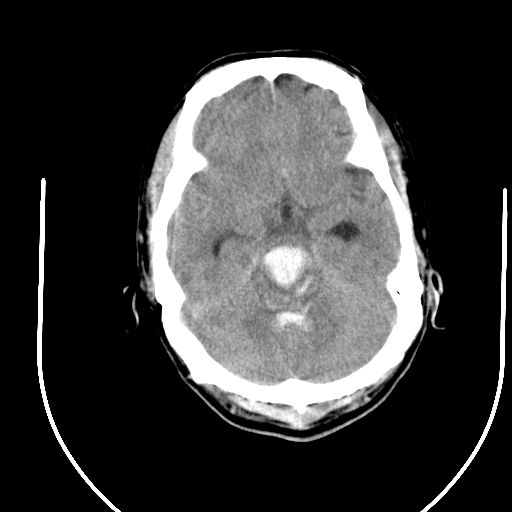

标题: CT24997:M,60Y,突发昏迷30分钟,有高血压病史。 [打印本页]

标题: CT24997:M,60Y,突发昏迷30分钟,有高血压病史。

1右侧基底节脑出血伴脑干出血并破入脑室系统脑疝形成2梗阻性脑积水

1)右侧基底节脑出血伴脑干出血并破入脑室系统。2)大脑镰下疝。3)梗阻性脑积水。

1、右侧基底节脑出血伴脑干出血并破入脑室系统。

2、大脑镰下疝。

3、梗阻性脑积水。